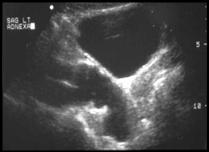

Transverse                          Sagittal